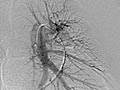

Angiogram of the Lung

An angiogram of the lung is an X-ray test that uses a special dye and camera (fluoroscopy) to take pictures of the blood flow in the blood vessels of the lung.

A lung (pulmonary) angiogram is used to check the arteries that lead to the lungs (pulmonary arteries) and the blood vessels in the lungs. It can also find narrowing or a blockage in a blood vessel that slows or stops blood flow.

Normal:

The dye flows evenly through the blood vessels.

No narrowing, blockage, bulging, or other problem of the blood vessels is seen. The pulmonary artery pressures are normal.

Abnormal:

Blood vessels that are not in their normal position may mean that a tumor or other growth is pushing against them.

A bulge in a blood vessel may mean a weakness in the blood vessel wall (aneurysm).

Dye that leaks out of a blood vessel may mean there is a hole in the blood vessel.

There is an abnormal vessel or blockage between vessels in the lung.

There is abnormal branching of blood vessels present since birth (congenital).